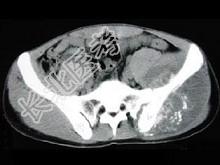

- 单项选择题男,35岁, 左髂部剧烈疼痛,尤以夜间明显, 可摸到肿物,结合图像, 最可能的诊断是 ( )

A、骨巨细胞瘤

B、软骨肉瘤

C、骨转移瘤

D、骨肉瘤

E、软骨瘤